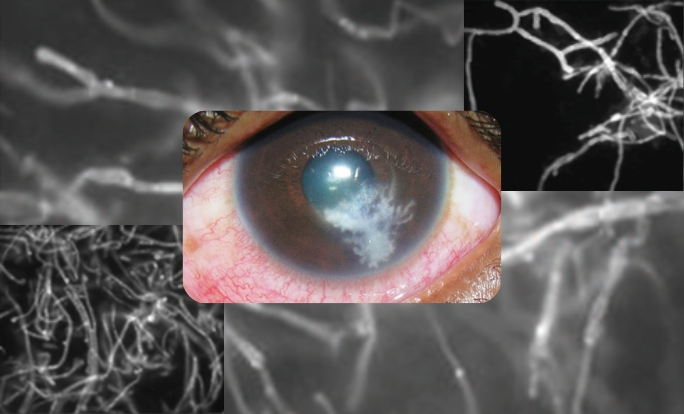

Identified unique pathogens causing “Keratitis”